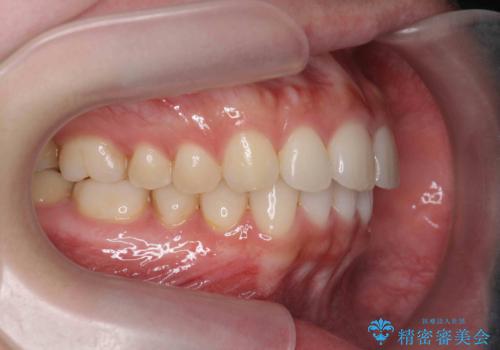

マウスピース 狭窄歯列の改善

- 噛み合わせが深い、笑った時の歯並びの改善を求めて来院されました。

マウスピース型の矯正装置インビザラインを用いた治療を計画します。

狭くなってしまった歯並びを放物線状に並べることで噛み合わせの安定・見た目の改善・ガタつきの改善を達成することができました。